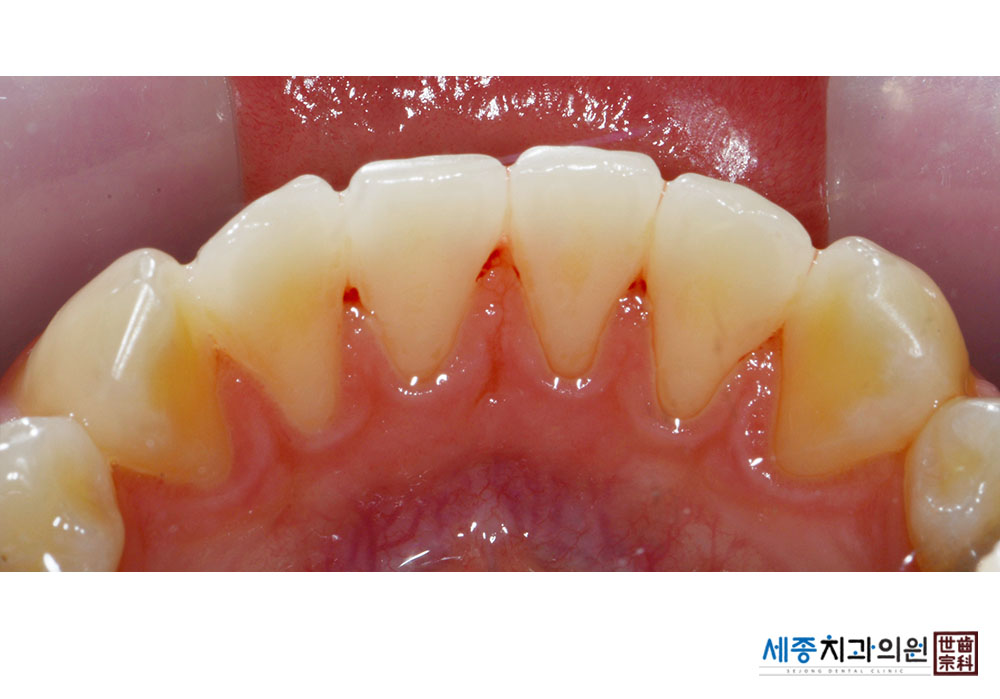

[스케일링] 치주질환 예방 스케일링

치료전 : 2022-05-11

치료후 : 2022-05-11

가글마취&저주파 스켈러를 사용한 스케일링